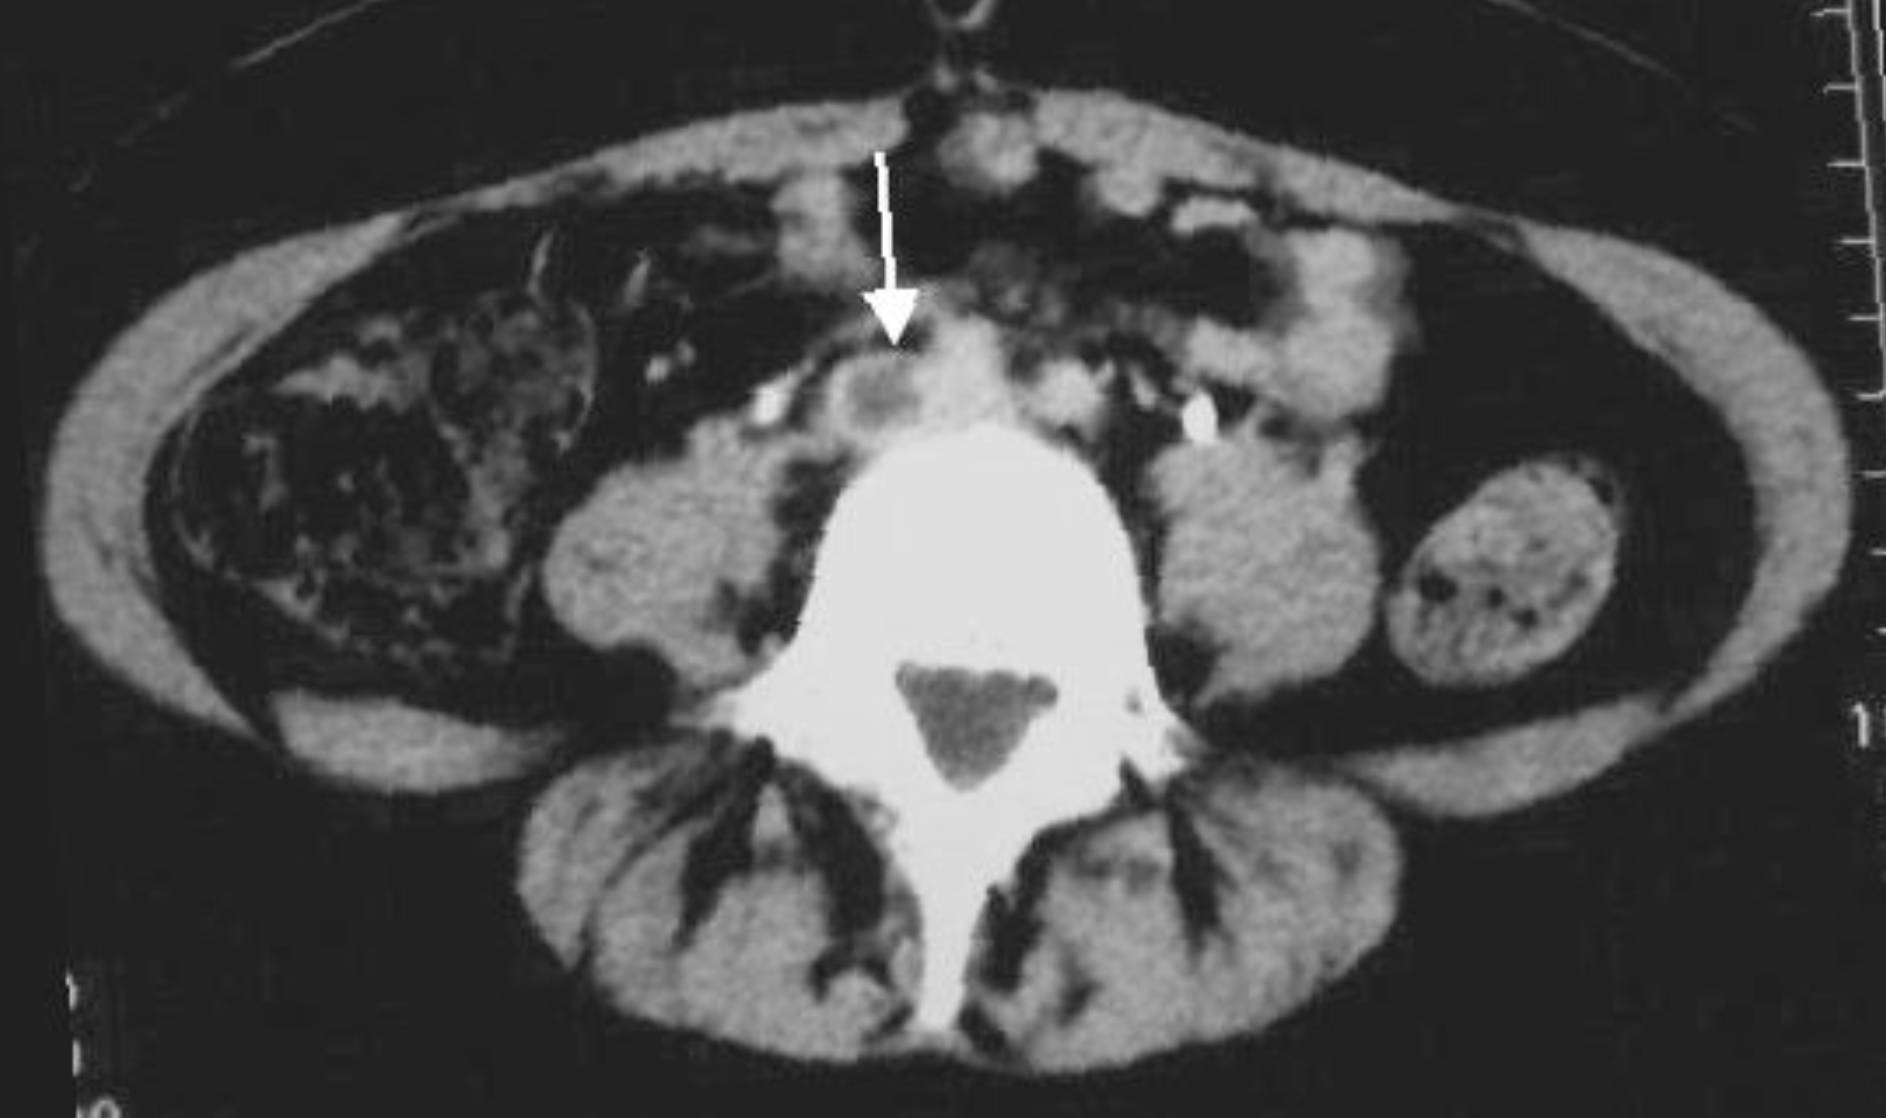

White arrow: The arrow points to a distinct filling defect located within the lumen of the right common iliac vein. Unlike the surrounding vessels which appear bright due to contrast enhancement, this area is dark and hypodense, indicating the presence of a solid thrombus (blood clot) obstructing normal blood flow.

Deep Vein Thrombosis (DVT) is a serious medical condition that typically occurs in the lower extremities, but it can extend proximally or originate in the large veins of the pelvis, known as the iliac veins. The image provided illustrates an axial CT slice of the abdomen, revealing a significant clot in the common iliac vein. Under normal circumstances, the iliac veins serve as the primary drainage pathways, carrying deoxygenated blood from the legs and pelvis into the inferior vena cava and back to the heart. When these vessels are obstructed, it creates a severe bottleneck in the venous system.

Diagnosing thrombosis in the pelvic veins presents a unique challenge compared to leg veins. While ultrasound is the gold standard for detecting clots in the thigh, sound waves often cannot penetrate deep enough to visualize the iliac veins due to interference from bowel gas and pelvic bone structure. Therefore, contrast-enhanced computed tomography (CT) venography is frequently utilized. As seen in the image, the CT scan allows for a clear cross-sectional view, differentiating between the patent (open) left iliac vein and the thrombosed (blocked) right iliac vein.

The abdominal CT scan is invaluable for assessment because it shows the “filling defect.” When contrast dye is injected into the bloodstream, it turns the liquid blood bright white on the scan. A clot, being a solid mass, does not absorb the dye and remains dark grey. In the provided image, the vertebral body (spine) is the bright white structure in the center, and the thrombosed vein is adjacent to it. Identifying this defect confirms the diagnosis and helps physicians measure the extent of the clot—specifically, whether it extends into the inferior vena cava.